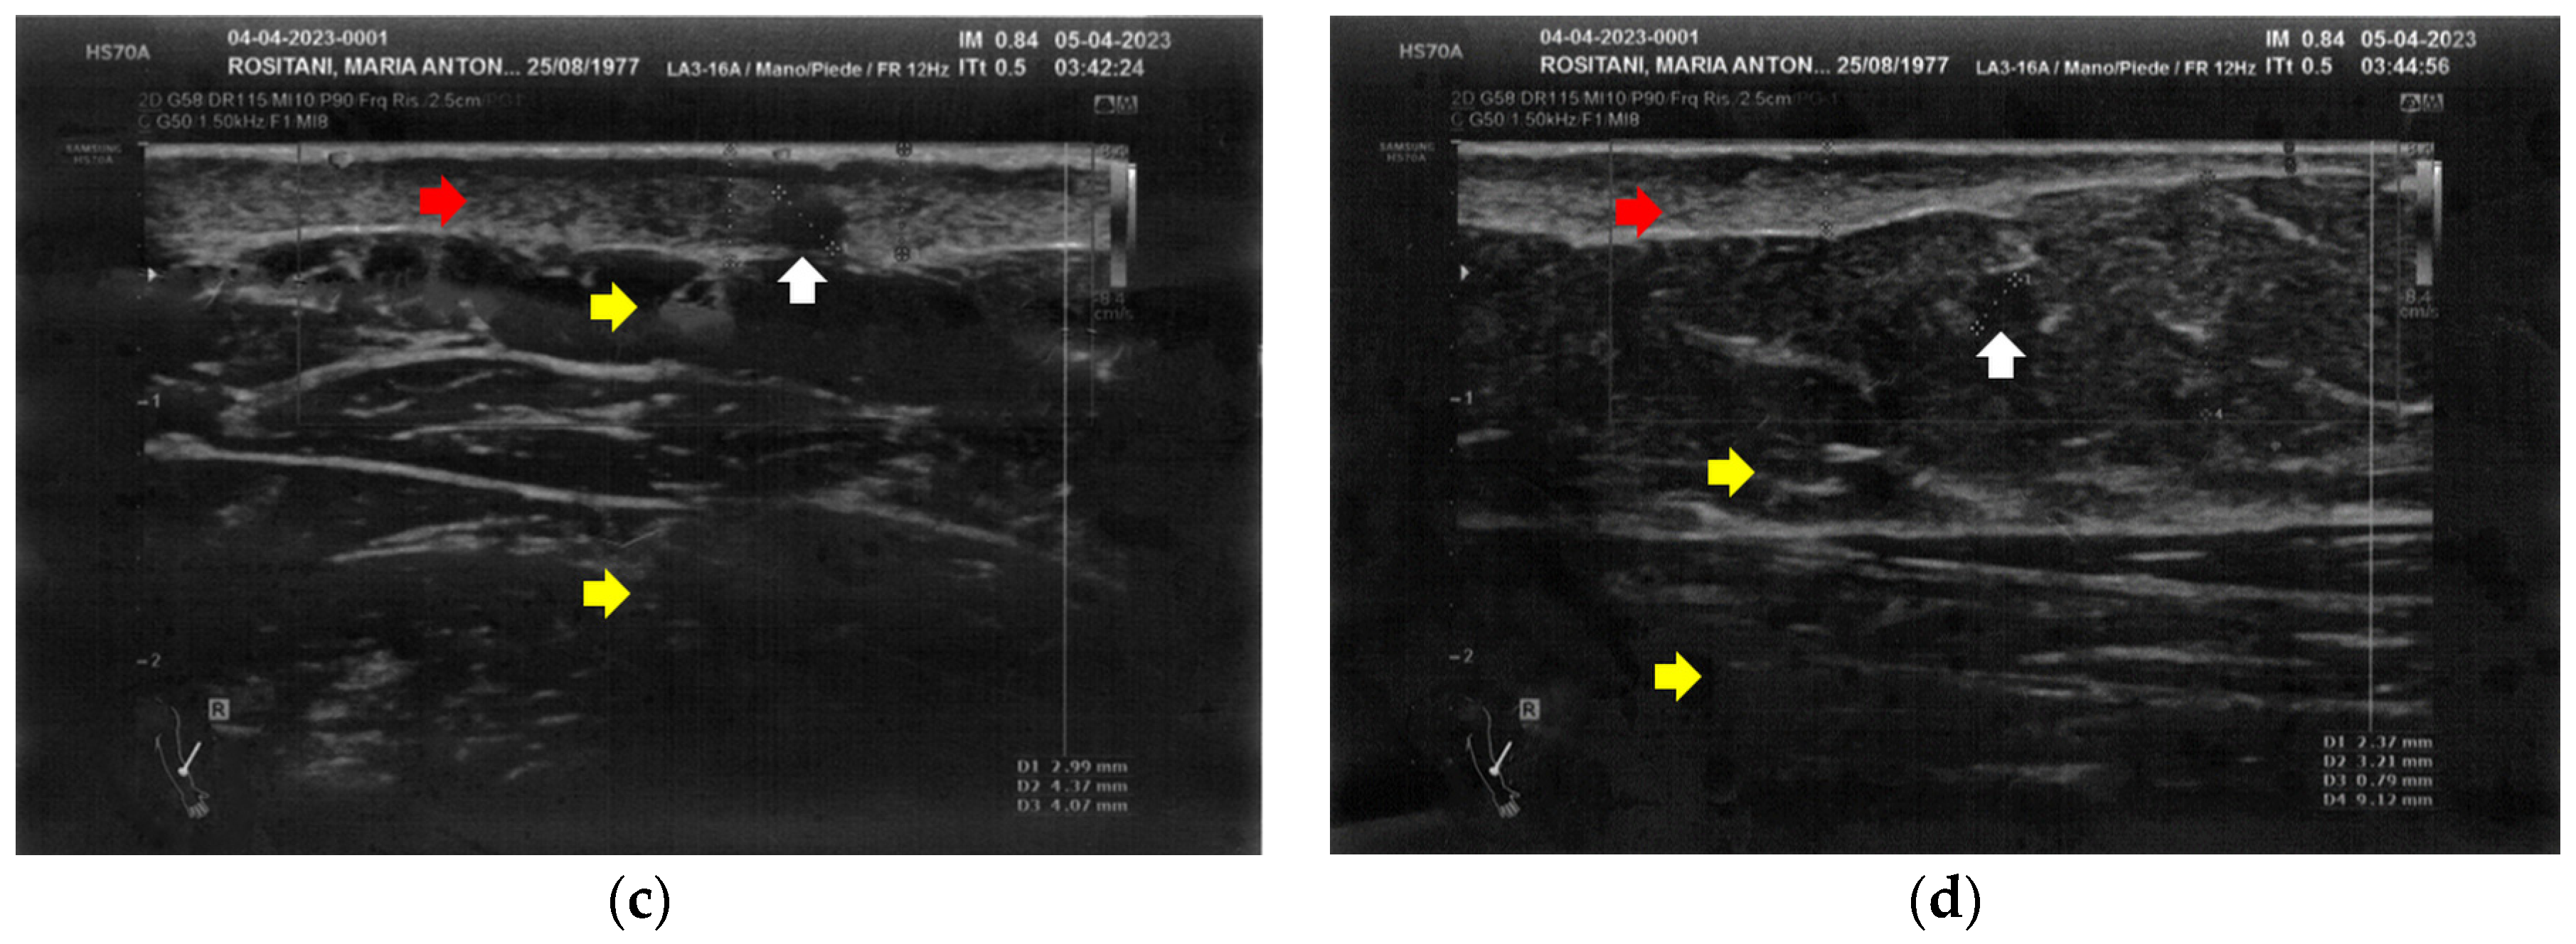

3.1. Basal Imaging Evaluations

3.2. Imaging Evaluations After the Treatment